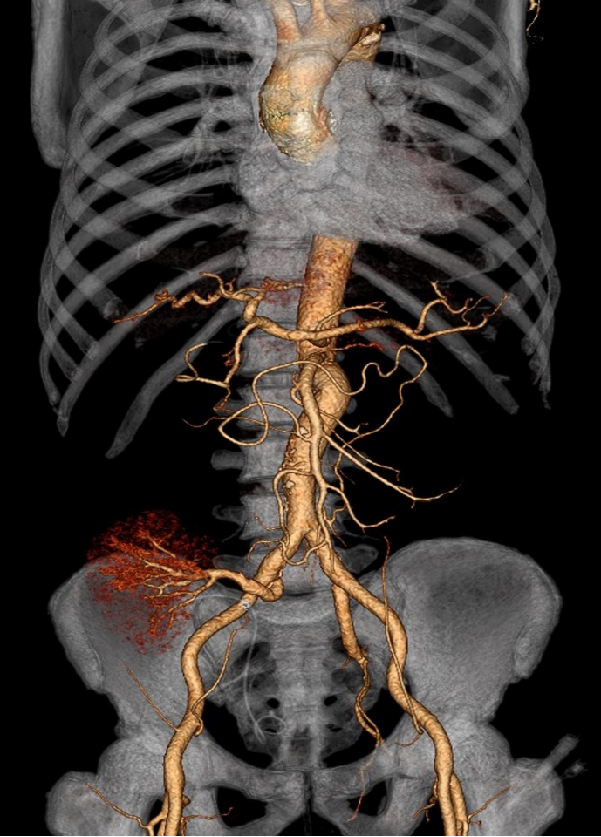

大动脉炎

男性,15岁

发现血压增高五年,双下肢乏力伴麻木一年余

最高血压达180/110mmHg。四年前行右肾动脉支架成形术,一年前复查时发现再狭窄,我院超声、CTA等相关检查提示“多发性大动脉炎”。

大动脉炎,主动脉及其主要分支广泛受累,多发节段性狭窄

右侧肾动脉近段支架置入,支架内腔稍变窄,右肾灌注尚可显影良好

左肾萎缩

手术方案:

腹主动脉-双侧髂动脉人工血管旁路术+右肾自体移植术

右肾移植于右髂窝,肾动脉与右髂内动脉吻合

术后5天复查CT

术后1年

术后3年